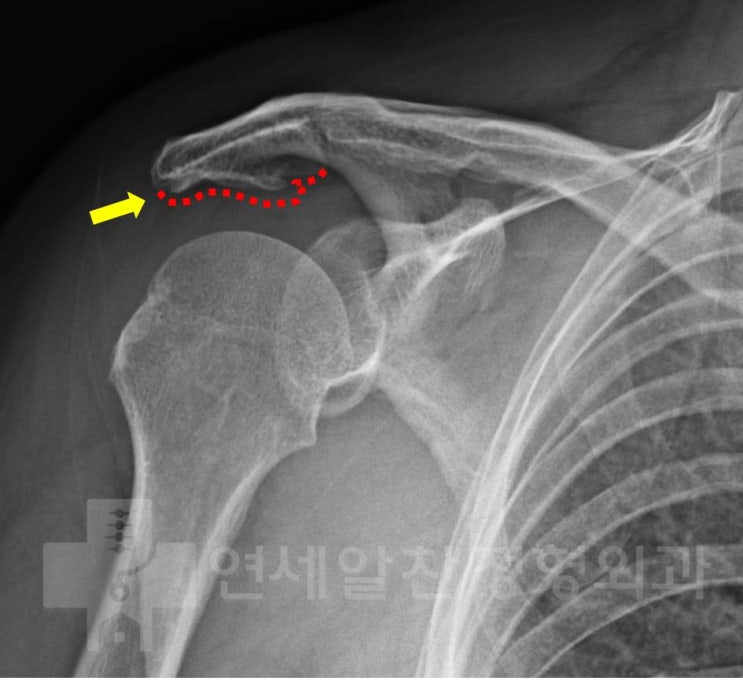

어깨 회전근개 파열 : 보다 단단하게 봉합하는 이열봉합법

안녕하세요. 정형외과 전문의 이동규 입니다. 오늘은 회전근개 파열에서 관절경 수술시 더 단단하게 봉합하...